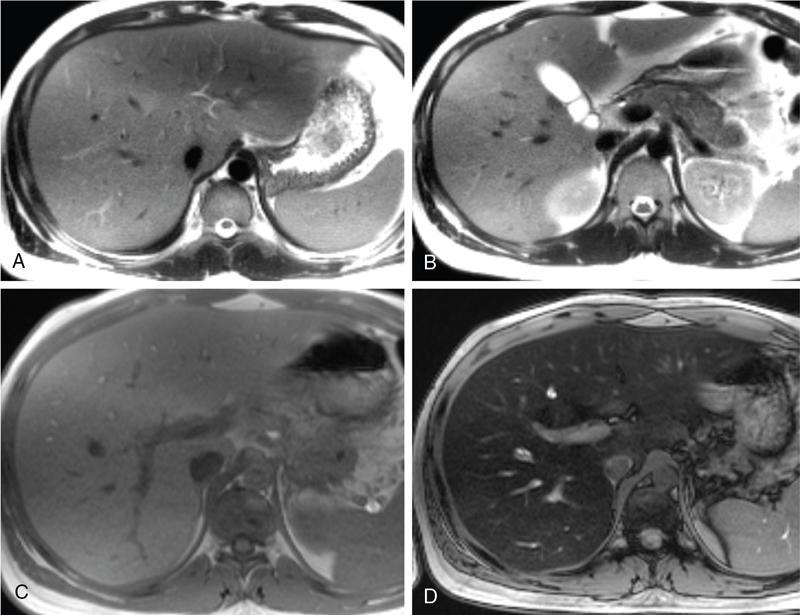

Excessive triglyceride accumulation within hepatocytes is defined as hepatic steatosis. Major conditions associated with hepatic steatosis include alcoholic fatty liver disease (AFLD) and nonalcoholic fatty liver disease (NAFLD). Causes of hepatic steatosis are discussed in Table 9.10.3. NAFLD is the most common form of hepatic steatosis and discussed in detail below. Up to 90% of patients with chronic alcoholic intake have fatty liver. Those with pure AFLD have a 10% risk of progressing to cirrhosis. Consumption of 30 g ethanol/day shows increased risk of chronic liver disease and cirrhosis. Other risk factors include female sex, obesity, cigarette smoking, obesity and associated risk factors. These factors are divided into 2 main categories which can cause fatty liver: inborn errors of metabolism and acquired metabolic disorders. Inborn errors of metabolism include abetalipoproteinemia, galactosemia, glycogen storage disease, hereditary fructose intolerance, homocystinuria and Wilson disease. Inflammatory bowel disease, jejunoileal bypass, malnutrition, starvation and total parenteral nutrition are acquired metabolic factors associated with increased risk. Chronic HCV infection, is associated with hepatic steatosis, with prevalence of 40%–80%. Hepatic steatosis can be seen as an adverse reaction to some medications such as tetracycline, valproic acid, some of chemotherapeutic agents, dexamethasone, amiodarone, methotrexate, tamoxifen and acetylsalicylic acid. Either microvesicular or macrovesicular steatosis can be observed in drug-induced hepatic steatosis. It generally occurs with therapy lasting several weeks or months and is reversible after discontinuation. The leading cause of hepatic steatosis in paediatric population is NAFLD. Six per cent of these patients develop cirrhosis and end-stage disease. Other less common causes include starvation and malnutrition, drugs (glucocorticoids, oestrogens, tetracyclines, and methotrexate), intoxications (carbon tetrachloride, organic phosphates, organic solvents, and alcohol), metabolic disorders, hepatitis C infection, and total parenteral nutrition. NAFLD is defined as steatosis affecting >5% of hepatocytes in the absence of a secondary cause. NAFLD represents a spectrum of disease, ranging from simple steatosis to steatohepatitis through to fibrosis and cirrhosis and in some cases hepatocellular carcinoma. NAFLD is a growing epidemic worldwide in part due to obesity and insulin resistance leading to liver accumulation of triglycerides and free fatty acids. Nonalcoholic steatohepatitis (NASH) is defined by histologic terms as a necroinflammatory process whereby the liver cells become injured in a background of steatosis. 20% of patients with NAFL progress to NASH, which progresses to fibrosis and cirrhosis over a 15-year time period (Fig. 9.10.3). The definition of NAFLD requires imaging or histology evidence of steatosis and no causes for secondary hepatic fat accumulation like significant alcohol intake, drugs or hereditary disorders (Table 9.10.4). The incidence of NAFLD ranges from 20% to 30% in Western countries and 5%–18% in Asia. As it currently stands, NAFLD represents the second most common reason to be listed for a liver transplant. The prevalence of NAFLD is higher in patients with obesity, diabetes, and patients with hyperlipidaemia. Prevalence increase with age from less than 20% at age 20 to more than 40% over 60 years of age. Males show a higher risk for progression to NASH and fibrosis (Table 9.10.5). Up to 90% of patients with NAFLD have simple steatosis, and about 30% of patients with NAFL develop NASH, and in again about 30%–40% of NASH patients the disease progresses to manifest fibrosis and cirrhosis NAFLD related cirrhosis has a 10-year mortality of 25% and a 5% chance of developing end-stage liver disease and HCC. The theory implicated in the pathogenesis of NAFLD is the two-hit theory. Insulin resistance, enhanced dietary influx and increased hepatic lipogenesis leading to accumulation of triglycerides (TG) and FFA in the hepatocytes is the first hit. The lipid peroxidation, mitochondrial dysfunction and inflammation resulting in hepatocyte damage and development of liver fibrosis is the second hit. The stages of NAFLD on histology range from steatosis initially to hepatic fibrosis in late stages. In the steatotic stage large (macro-) and small (micro-) vesicles of fat, predominately triglycerides, accumulate within hepatocytes. The affected parenchyma is divided into thirds: 5%–33%, 34%–66% and >66% and graded as mild, moderate and respectively. Ballooned hepatocytes with accompanied steatosis and inflammation are characteristic of the steatohepatitis stage. Fibrosis has a characteristic appearance with early lesions showing a perisinusoidal deposition followed by periportal fibrosis which progresses to bridging. Raised GGT is the most common liver enzyme elevated in NAFLD. Transaminases are within normal range in 80% patients. No specific blood tests can diagnose NAFLD. Liver biopsy has remained the gold standard for diagnosis and quantification of liver fat. Drawbacks, however, include invasive nature, sampling error and procedure related complications like bleeding. Various imaging techniques are currently available in diagnosing and quantifying liver fat. MRI in particular proton density imaging and MR Spectroscopy have revolutionized imaging of fatty liver. Normal liver parenchyma is the same as or slightly more echogenic than the adjacent kidney and spleen. Fat deposition leads to increased echogenicity of liver. Decreased beam attenuation in patients with fatty change leads to poor visualization of structures such as intrahepatic vessels, bile ducts and liver lesions and in severe cases diaphragm (Table 9.10.6). Fatty liver can be graded on USG as: US has a fair accuracy of detecting the moderate to severe hepatic steatosis with sensitivity of about 90% and specificity of about 95% for patients without concomitant chronic liver disease. Ultrasound is observer and equipment dependent. Confounding factors such as large body hiatus may lead to overestimation of hepatic steatosis due to beam attenuation by overlying fat. Conditions like fibrosis, inflammation can affect interpretation. The ratio between the mean brightness level of liver and right kidney is called the Hepatorenal sonographic index. A cut off of 1.49 has a high sensitivity and specificity for diagnosis of steatosis >5%. The main advantages of CT for assessing steatosis are relatively fast acquisition, ease of performance, and quantitative results. Estimation of fatty liver is done on non-contrast enhanced images. The normal liver density is around 60 HU, which is approximately 10 HU higher than normal spleen. Fat accumulation in the liver manifests as proportionate decrease in density. Both the absolute and relative (to the spleen) values are used to characterize steatosis; a cut-off value of 40 HU has been suggested to predict fat content greater than 30% (Figs. 9.10.6 and 9.10.7) Attenuation difference between liver and spleen on unenhanced CT scan is a commonly used quantitative parameter to evaluate hepatic steatosis. This avoids errors in attenuation value measurement from different CT scanners and different reconstruction algorithms. Normal liver parenchymal attenuation on nonenhanced CT is slightly higher than the spleen. Liver attenuation progressively decreases as percentage steatosis increases (Table 9.10.7) (Fig. 9.10.8) Methods of liver fat quantification on CT have been discussed in details in chapter on liver transplant. Limited diagnostic accuracy for detecting mild degree hepatic steatosis is one of major drawback of CT. Disorders causing hyperdensity of liver such as iron, glycogen deposition can lead to errors in interpretation. The concomitant presence of iron and fat may not be accurately diagnosed on CT. Low CT density values may also be caused by oedema and inflammation. Likewise, the spleen is an imperfect reference standard as it can be affected by haemosiderosis and haemochromatosis in a small minority of patients. Dual-energy CT with its ability to perform material decomposition is more accurate in quantifying hepatic steatosis and allows staging of fibrosis. Imaging is done with two different energies (typically 80 kVp and 140 kVp). DECT has the potential to quantitate liver fat content independent of ROI (region of interest) placement. Magnetic resonance imaging (MRI) is presently the most accurate imaging modality for the evaluation of hepatic steatosis. Several different methods have been developed and introduced in MRI for the evaluation of hepatic steatosis. In this technique typically, two gradient echoes are acquired, one employing a TE in which the water peak (4.7 ppm) and the dominant fat peak (1.3 ppm) are ‘out of phase’ and hence subtractive (SOP), and the other using a TE in which the two peaks are ‘in phase’ and therefore additive (SIP). Because two echoes are acquired, this is often called ‘dual-phase’ or ‘dual echo’ imaging. Fat Signal Percentage is calculated as [SIP – SOP]/[2 × SIP] ×100. The dynamic range of magnitude based chemical shift techniques has typically a 0%–50% signal fat-fraction (Fig. 9.10.9) This technique uses both magnitude and phase information from three or more images acquired at different echo times appropriate for more accurate separation of water and fat signals as against only magnitude information in dual-echo. These methods provide estimates of fat fraction with a dynamic range of 0%–100%. Proton density Fat fraction (PDFF) is calculated as Sf/(Sw + Sf) where Sw = SI of the water component, Sf = SI of the fat component. PDFF specifically reflects the concentration of triglycerides in the hepatocytes as lipids within the other structures such as cell membranes and organelles are occult. Sensitivity up to 96% and specificity up to 100% for detecting any degree of steatosis have been reported. A fat-fraction threshold of 5.56% is commonly used to define steatosis; however, the optimal cut-off value still needs to be defined (Figs. 9.10.10 and 9.10.11). MRS can directly measure the chemical composition within tissue based on the frequency composition of the signal originated from the voxel of interest. Water proton peak appears as a single peak at 4.7 ppm, whereas fat peaks appear as multiple peaks around 1.3 ppm. PDFF can be calculated as the ratio of the sum of the signal intensities derived from the protons in fat divided by the sum of the signal intensities originated from the protons in both fat and water (Fig. 9.10.12). TABLE 9.10.8 MRS data are usually obtained from a single voxel manually placed in the liver parenchyma usually right posterior segment of the liver. Reported MRS sensitivities and specificities for detection of mild hepatic steatosis are 80.0%–91.0% and 80.2%–87.0%, respectively, outperforming CT and US. MRS can also provide excellent reproducibility of measurement. It is also unaffected by confounding factors like fibrosis, iron overload and glycogen. Small sample volume usually less than 3 × 3 × 3 cm3 is a major limitation of MRS, particularly in patients with uneven fatty change. Despite these practical limitations, MRS is considered to be the gold standard MR method for hepatic fat quantification. This is the most frequently encountered pattern and considering the homogenous involvement poses no diagnostic dilemma. Focal fat deposition and focal sparing in diffuse fatty liver are less common. These usually occur in specific locations like adjacent to falciform ligament or ligamentum venosum, in portal hepatis or gallbladder fossa. Imaging findings are suggestive of fatty pseudolesions rather than true masses. Occurrence in characteristic locations, absence of mass effect on vessels and structures, geographic configuration and contrast enhancement similar to or less than adjacent liver (Fig. 9.10.13). Fat deposition around insulinoma metastasis can occur as a local effect of insulin on the liver parenchyma. On ultrasound, it appears as an echogenic rim shows signal drop on out of phase images. Eisenberg has reported perilesional steatosis around focal nodular hyperplasia. Sometimes multiple small foci and seen scattered throughout the liver. These may appear as small round nodules (Fig. 9.10.14). Opposed phased imaging is more useful than CT or US to establish diagnosis. These may, however, pose a diagnostic dilemma in patients with known malignancy. Perivascular fatty infiltration is a recently described entity, mostly seen in alcoholic patients. This pattern is characterized by halos of fat that surround the hepatic veins, the portal veins, or both hepatic and portal veins (Fig. 9.10.15). Normal vessels coursing through the lesion without attenuation in calibre suggest the diagnosis. Peritoneal dialysis with insulin in the dialysate in patients with renal failure and insulin-dependent diabetes. Exposure of subcapsular hepatocytes to a higher concentration of insulin results in fat deposition in the subcapsular regions. Some hepatic lesions such as hepatic adenoma, hepatocellular carcinoma, regenerative nodules and focal nodular hyperplasia can show intracellular steatosis (Fig. 9.10.16). These areas show signal drop on opposed phase. However, postcontrast imaging characteristics of these lesions allow differentiation from areas of focal steatosis. Perilesional sparing has been reported in haemangioma and hepatocellular carcinomas. This may mainly represent decreased portal flow due to either compressed or atrophic hepatocyte cords in expanding metastases or arterioportal perfusion abnormalities in haemangiomas. The differential diagnosis of focal fat infiltration is discussed in Table 9.10.9. Accurate history and chemical shift imaging showing signal drop help in differentiation of focal fat from metastasis. These are visible only during the arterial and portal venous phases after contrast agent administration. The morphologic appearance of fat deposition and perfusion abnormalities is similar. Perfusion abnormalities however are visible only during the arterial and portal venous phases (Fig. 9.10.17). They are not seen as an attenuation difference on nonenhanced CT. Periportal oedema, inflammation, haemorrhage and lymphatic dilatation may mimic perivascular fat. With the exception of haemorrhage all other conditions affect periportal region symmetrically (Fig. 9.10.18). Patients with haemorrhages may show other signs of injury. Chemical shift imaging is helpful in cases with diagnostic challenges.

Patterns of fat deposition

Diffuse deposition

Focal deposition and focal sparing

Perilesional steatosis

Multifocal deposition

Perivascular deposition

Subcapsular deposition

Intracellular lipid containing lesions (intratumoural or intralesional steatosis)

Perilesional or peritumoural fatty sparing